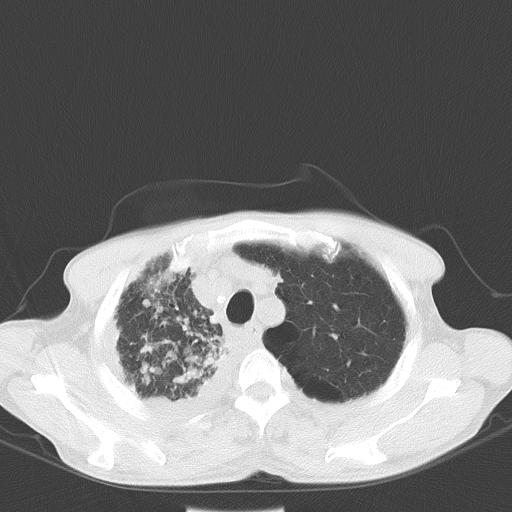

男性 75  咳嗽 一周前发热最高达39

右肺继发型tb并右侧tb性胸腔炎,右侧胸腔大量积液并右下肺膨胀不全,慢支肺气肿、多发肺大泡。建议抽胸水实验室检查并复查排除恶性在占位。

右上肺继发型肺结核,右胸腔中等量积液。

左上肺大泡。

结核的基础上有纵隔淋巴结肿大,右侧有胸水,但右侧纵隔反而窄,说明有肺有不张。

再就是右下肺有块影,和不张混合,还是不能除外肺癌。

1)右肺继发型肺结核。2)左肺胸膜下多发性肺大泡。3)右侧胸腔积液。